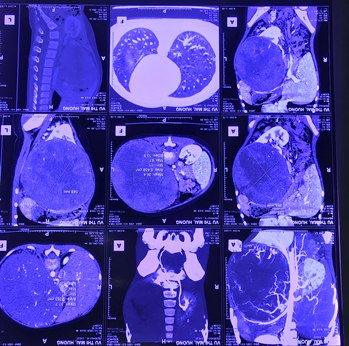

Bệnh nhi Vũ Thị Mai H (6 tuổi ở Nghệ An) được chẩn đoán ban đầu có u sau phúc mạc. Các bác sĩ Khoa Ngoại Bụng 2 và Khoa Nhi (Bệnh viện K) đã hội chẩn, dựa trên triệu chứng lâm sàng, yếu tố dịch tễ, phim chụp cắt lớp vi tính, mô bệnh học và đặc biệt là kết quả hóa mô miễn dịch xác định đó là u nguyên bào thận trái (u Wilm); đồng thời thống nhất phác đồ điều trị, sau đó tiến hành phẫu thuật.

Phim chụp khối u thận ở bệnh nhi. Ảnh: Bệnh viện K TƯ.

Sau khi thăm khám và chụp chiếu, bác sĩ phát hiện bệnh nhi có khối u lớn khoảng 20 cm, chèn ép nhiều bộ phận gây đau tức, ảnh hưởng lớn đến hô hấp cũng như sinh hoạt của bệnh nhi.